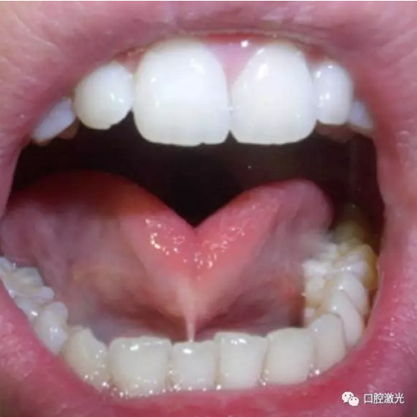

口腔中的系帶一般分為舌系帶和唇系帶,其中唇系帶又可分為上唇系帶和下唇系帶。如果嬰幼兒出現(xiàn)口腔系帶問(wèn)題,一般會(huì)導(dǎo)致無(wú)法哺乳、吞咽困難、語(yǔ)言障礙等問(wèn)題,嚴(yán)重影響兒童發(fā)育。

正常的舌系帶同樣應(yīng)該允許舌部的自由運(yùn)動(dòng),尤其是舌部在吞咽、語(yǔ)言以及牙齒和頜部的發(fā)育中扮演重要的角色。對(duì)于舌系帶過(guò)短的兒童患者,一般常見(jiàn)以下危害: